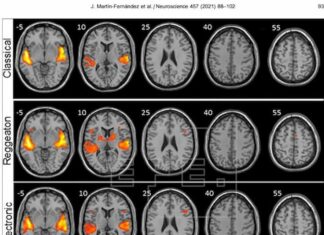

Investigadores dicen que el reguetón provoca mayor actividad cerebral que escuchar...

Santa Cruz De Tenerife(España).- Frente a la música clásica, el folclore y la electrónica, el reguetón provoca una mayor activación en las regiones del...